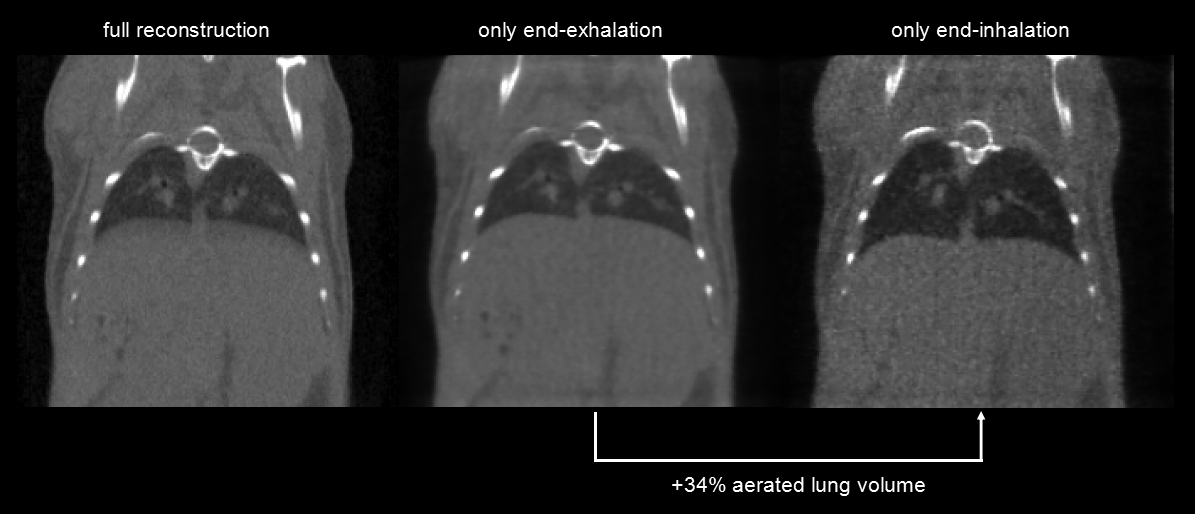

5、ECG/respiratory gated CT imaging

Respiratory gating: Ultra-high temporal resolution (10ms), 4min, 390mGy. Left: Integrated picture. Middle image: at the end of the exhalation and right image: at the end of the inhalation show a 34 percent difference in the volume of the lungs.

圖13. 呼吸門控.png